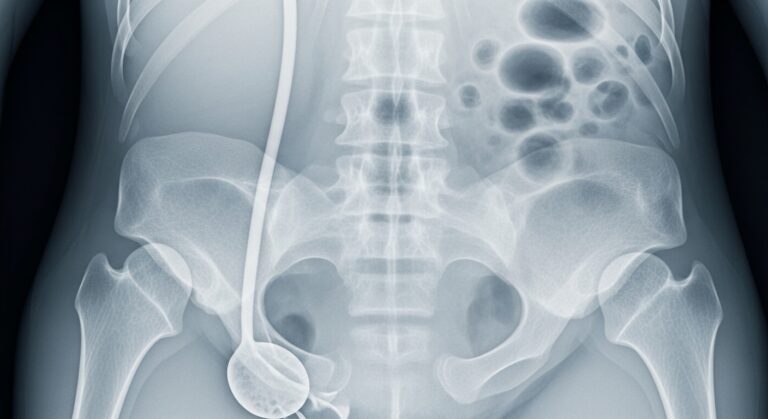

– Scopy, Röntgen

– Röntgen, Echo, MRI scan

– Pelvin floor therapy, Scopy